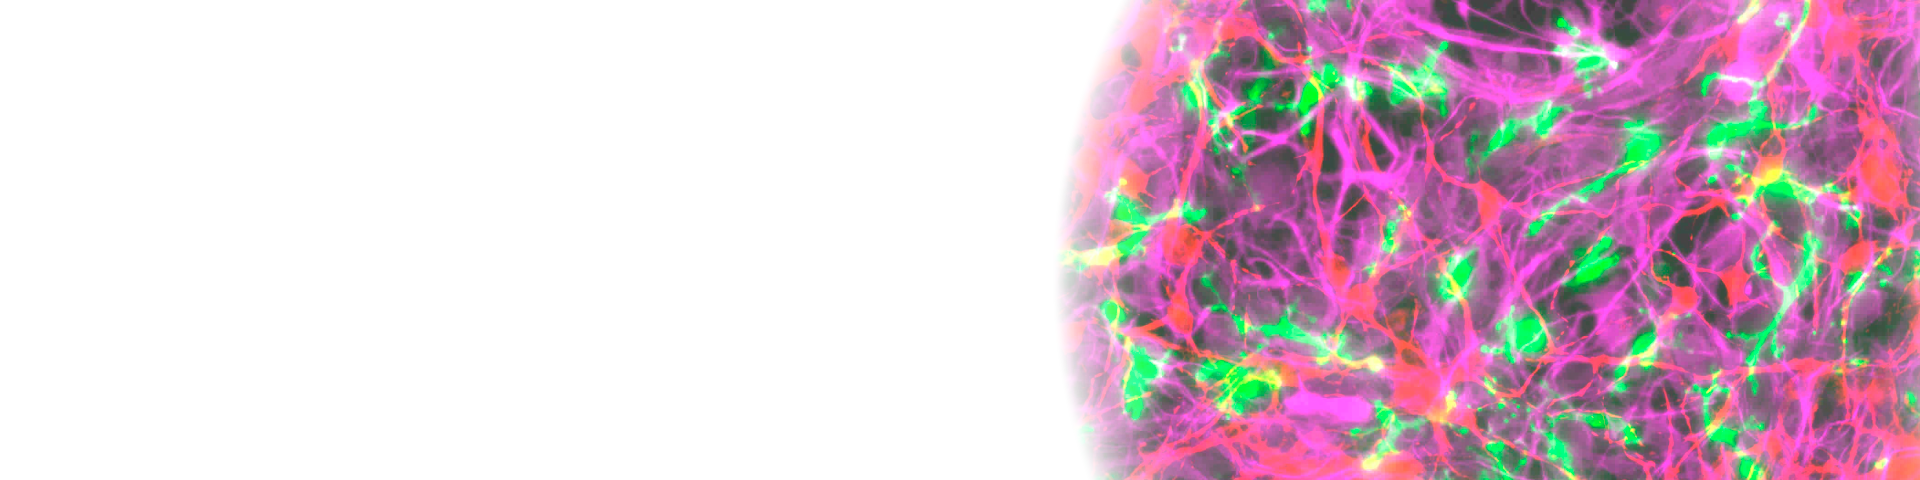

- Neurotoxic human iPSC-astrocytes and gene expression network analysis to identify drug targets for neurodegenerative diseases (Hayato Kobayashi, Kiyohiro Maeda, Kenichi Kazetani, Akira Nabetani, Setsu Endoh-Yamagami)